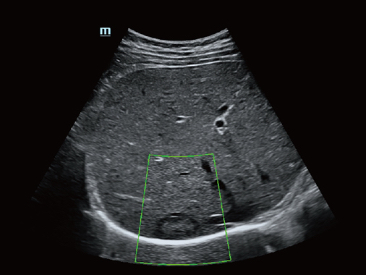

Desde que se fund├│ la compa?├Ła, Mindray ha explorado incansablemente nuevas formas de mejorar la confiabilidad del diagn├│stico. Con la revolucionaria tecnolog├Ła de ZONE Sonography?, la nueva plataforma ZST+ de Resona?7 lleva la calidad de la imagen por ecograf├Ła a un nivel superior mediante el procesamiento de datos de canal y la adquisici├│n de zona.

Adem├Īs de la calidad de imagen de primer nivel, Resona?7 tambi├®n mejora las capacidades de investigaci├│n cl├Łnica con el revolucionario V?Flow para la evaluaci├│n hemodin├Īmica vascular y con la adquisici├│n de planos m├Īs inteligente a partir de conjuntos de datos 3D para el diagn├│stico del SNC fetal. Al combinar el funcionamiento multit├Īctil basado en gestos m├Īs intuitivo y todas las caracter├Łsticas cl├Łnicas esenciales, Resona?7 realmente lidera las novedades en innovaci├│n de ecograf├Łas.